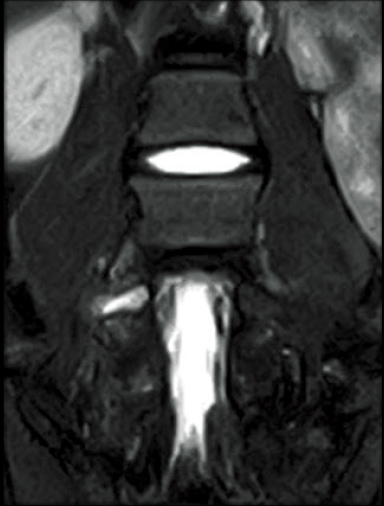

T2WI